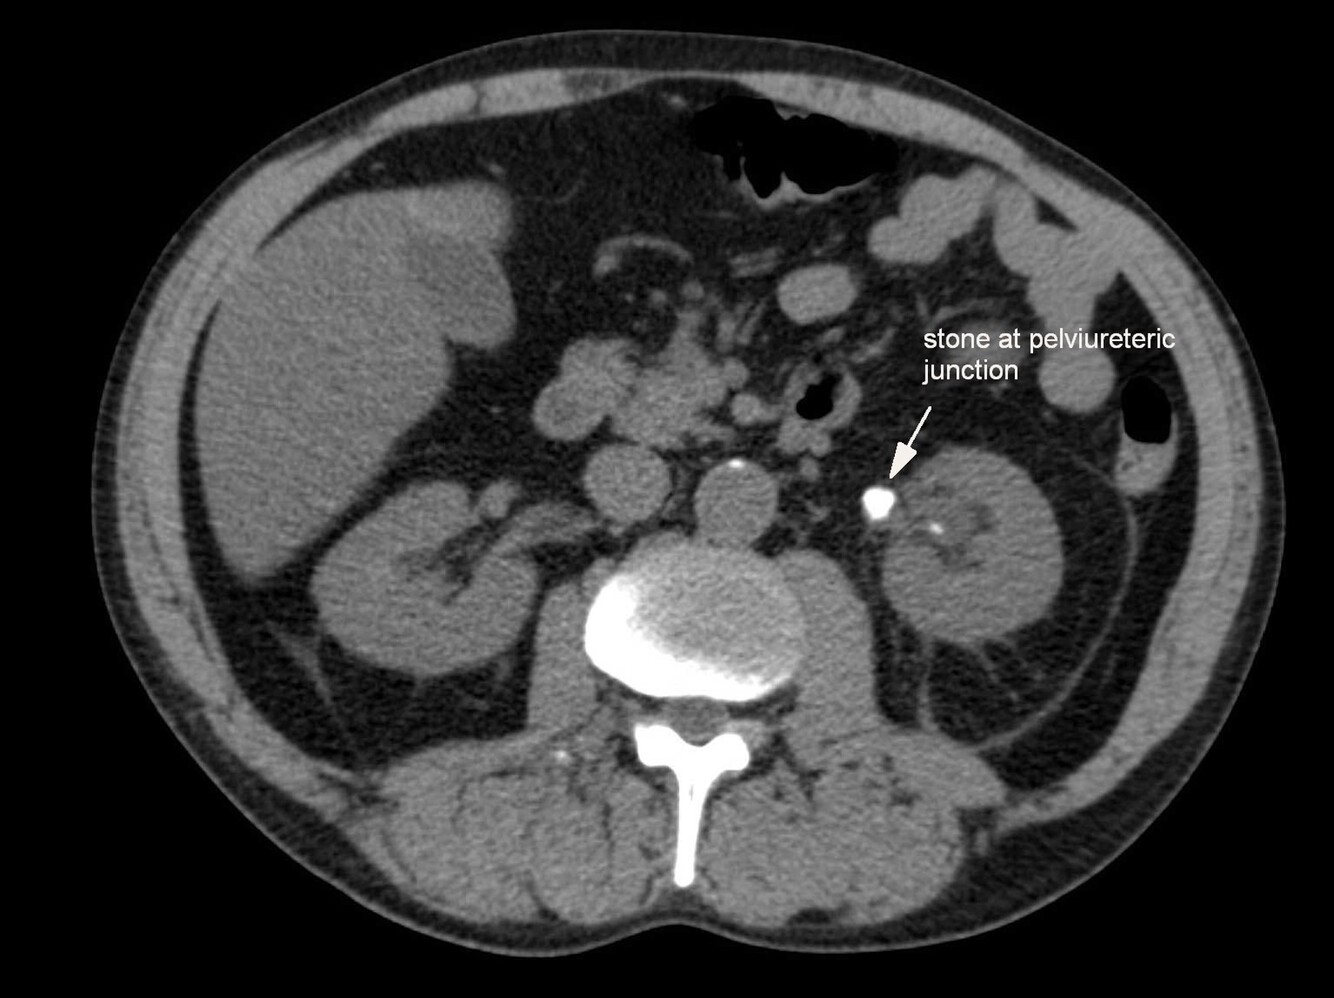

23

Q

What pathology is seen here?

A

Urinary Calculi